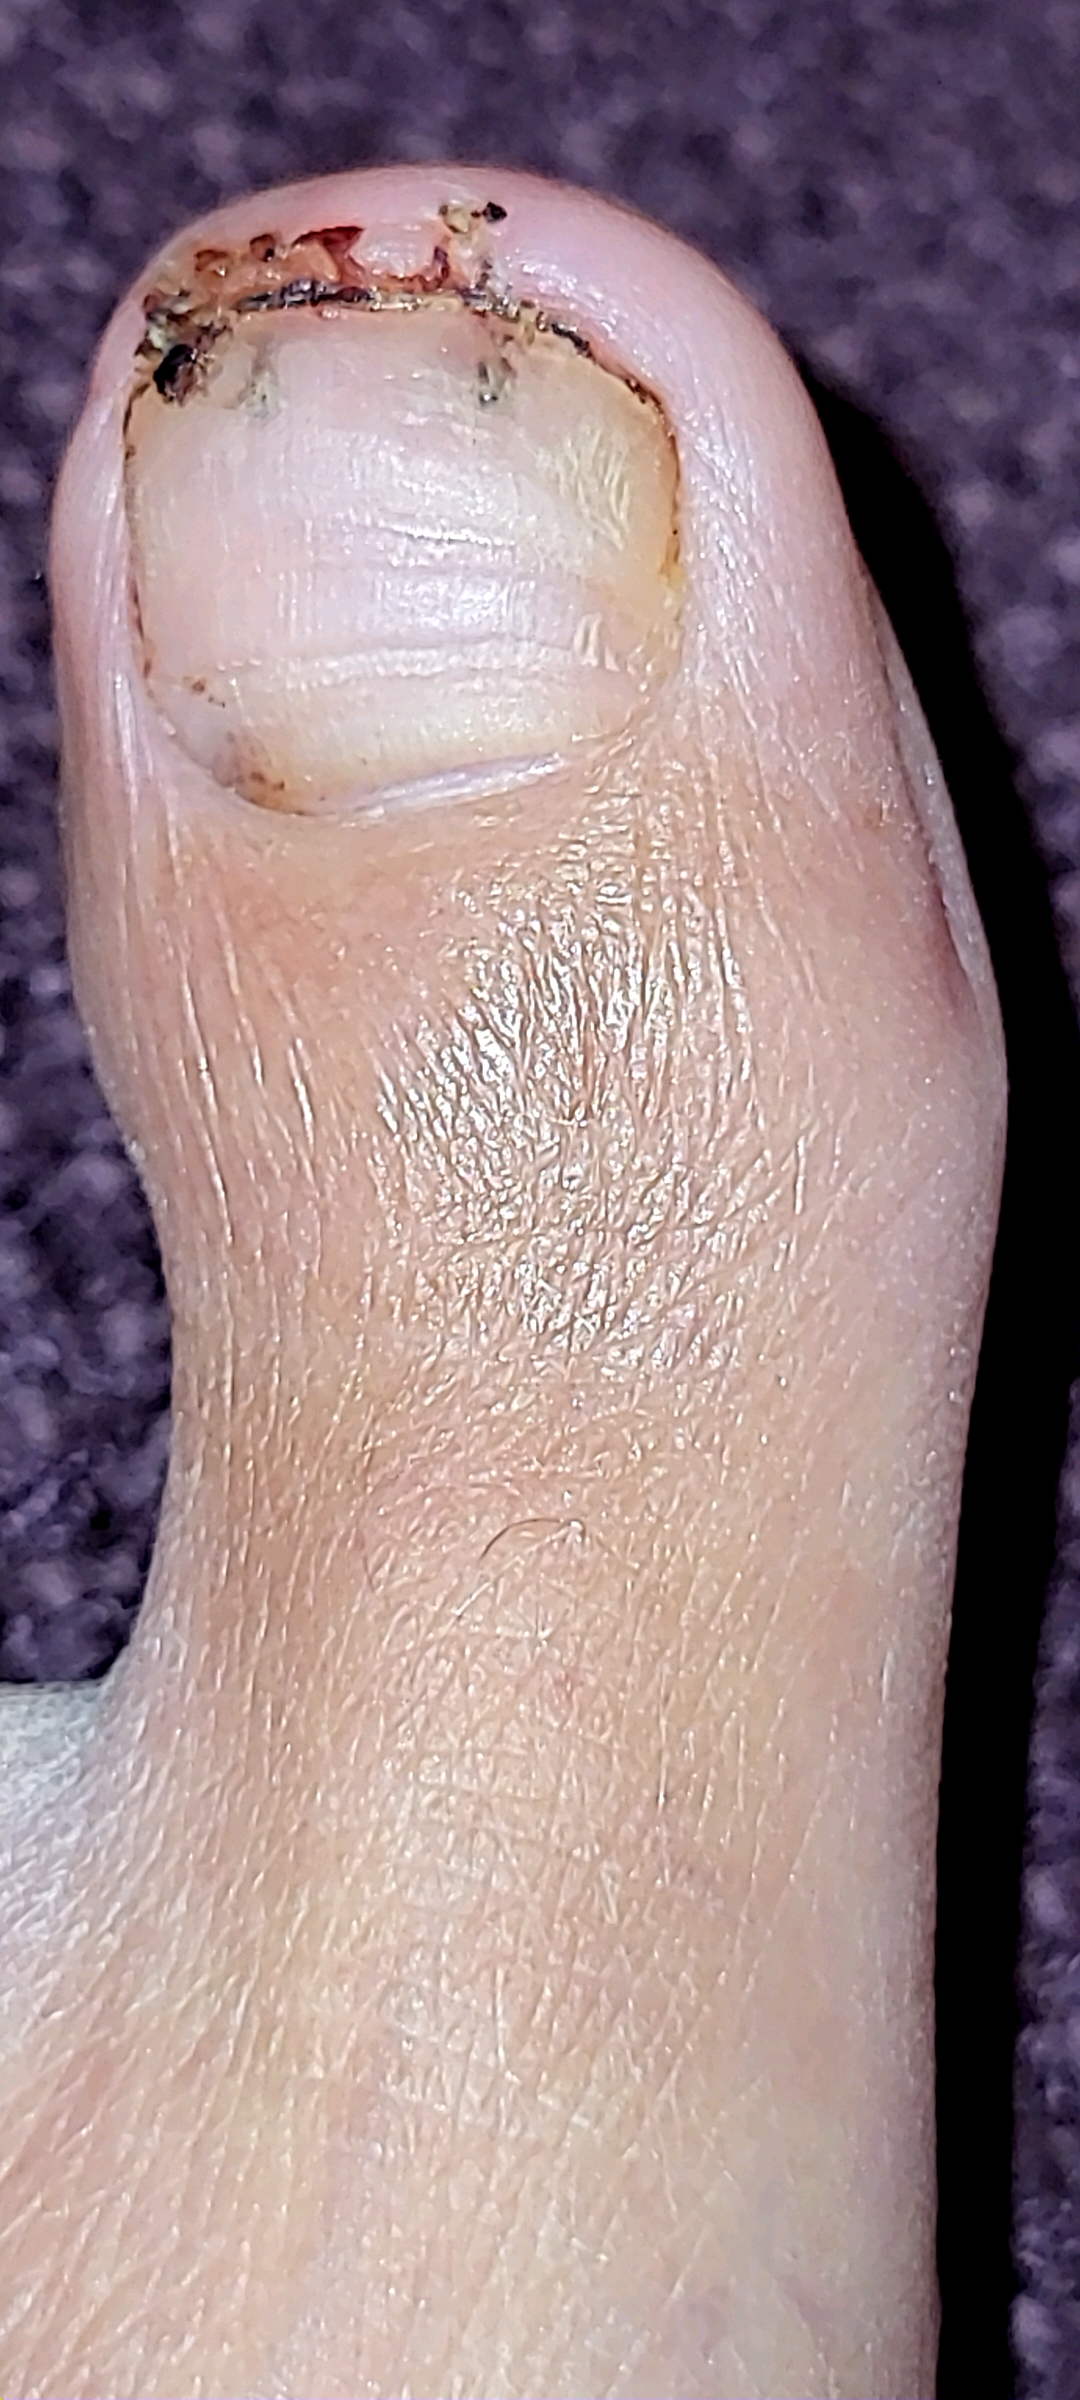

Left Great Toe 6 weeks post second bone (lateral) debridement surgery & left / right Great Toe comparisons:

Left Great Toe 12 weeks post first bone debridement surgery & left / right Great Toe comparisons:

post first bone debridement surgery (medial side)